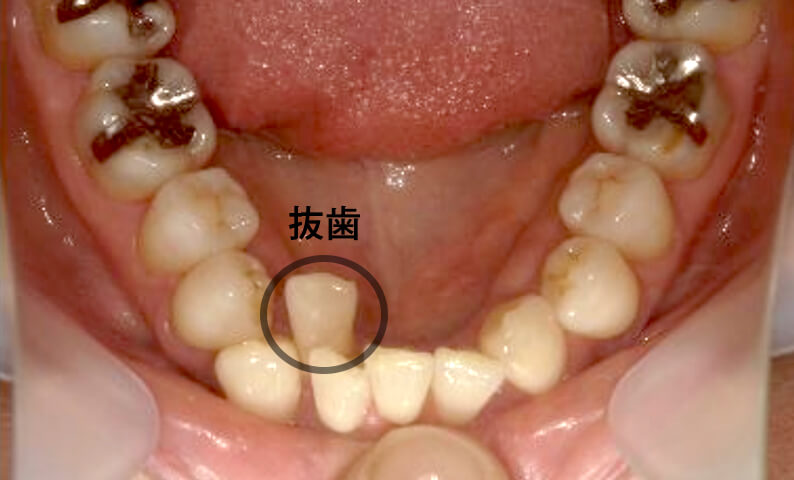

症例_003 下顎だけの部分矯正

治療期間:10ヶ月金額:24万円+税女性前歯のガタガタ下の前歯だけ上顎は補綴治療中

| Before | After |